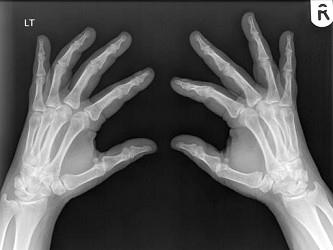

男,请根据其正常手的影像图像,判断其最可能的年龄 ( )A、76岁左右B、56岁左右C、26岁左右D、36岁左右E、16岁左右

问题 男,请根据其正常手的影像图像,判断其最可能的年龄 ( )

选项 A、76岁左右 B、56岁左右 C、26岁左右 D、36岁左右 E、16岁左右

答案 B